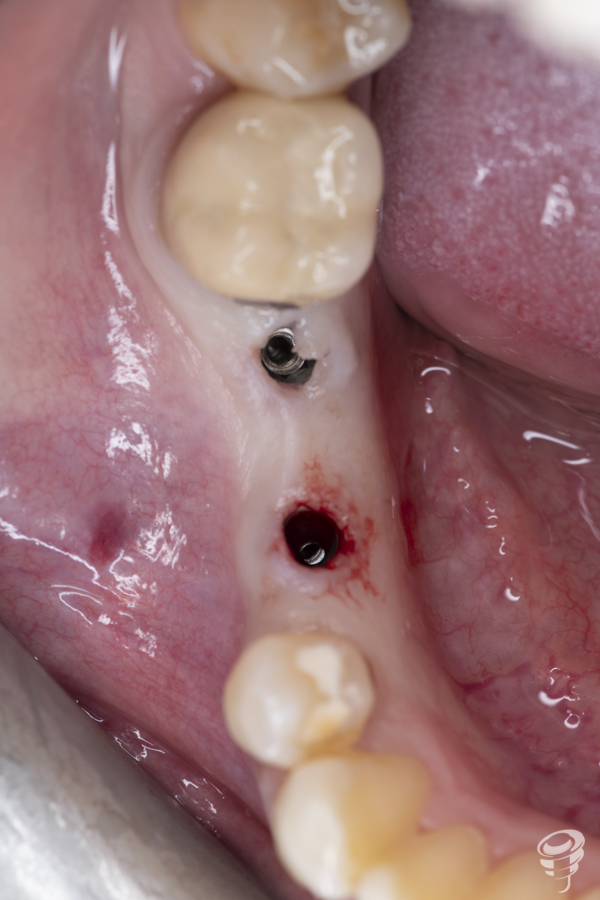

Colocación de implantes y componentes protésicos

Una vez realizada la expansión ósea, se insertan los dos implantes Galimplant de 4 mm de diámetro y de 10mm de longitud (IPX 4010). Estos implantes son de titanio grado IV con conexión cónica a 11 grados. Una vez colocados los implantes, retiramos el porta implantes con un mosquito e insertamos 2 pilares multi-posición rectos estéticos altura 3mm (MUSR04030)

La colocación inmediata de estos pilares es fundamental para la obtención de resultados óptimos. No sólo es necesario que el implante se integre , sino que además es necesaria una relación optima entre la conexión del implante, el pilar protésico y un buen sellado biológico, la cual, en muchos casos, se ve alterada por la conexión y desconexión de diferentes pilares durante la fase de oseointegración y restauración del implante.